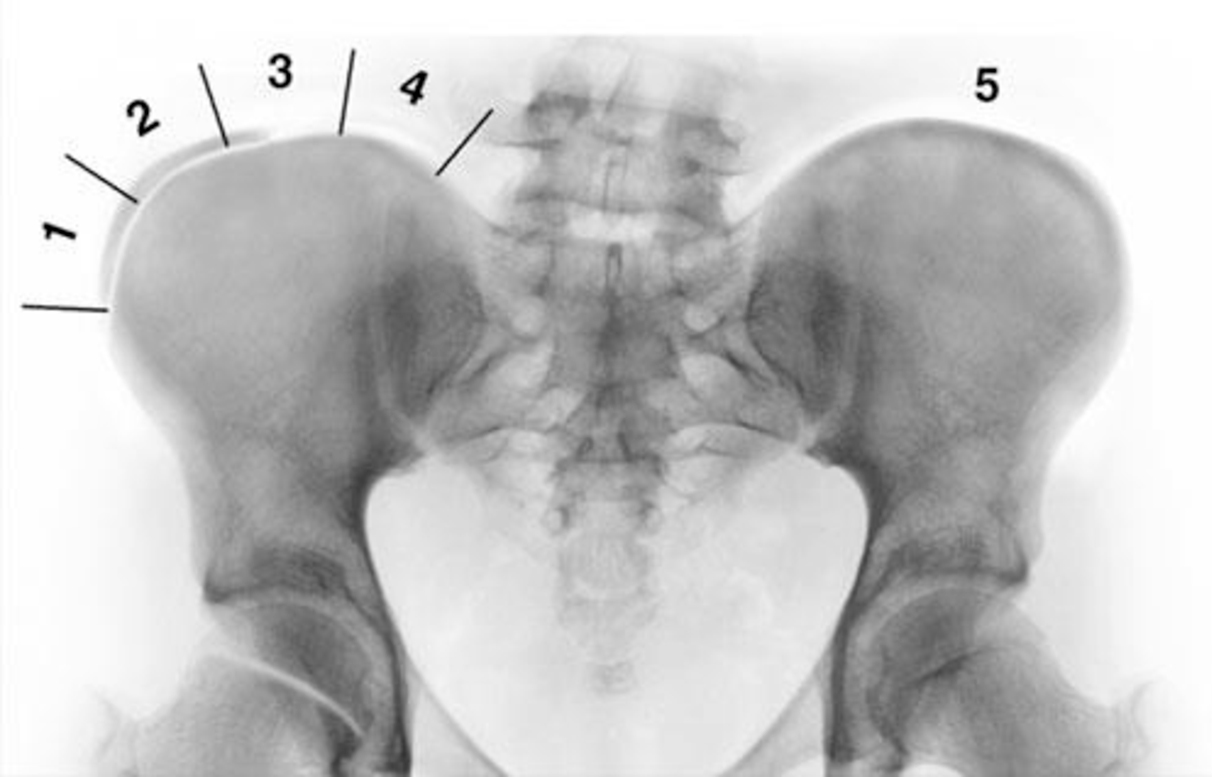

THE RISSER SIGN

The Risser sign describes a phase of skeletal maturity based on the observation of the iliac crest ossification stage. The ossification process starts from the most lateral portion of the iliac apophysis and continues until the whole iliac crest is completely fused.

Although the Risser sign is still widely used by clinicians, such a diagnostic tool does not provide any information about the initial stages of development. The ossification centre, indeed, is observed initially towards the end of the peak growth spurt.